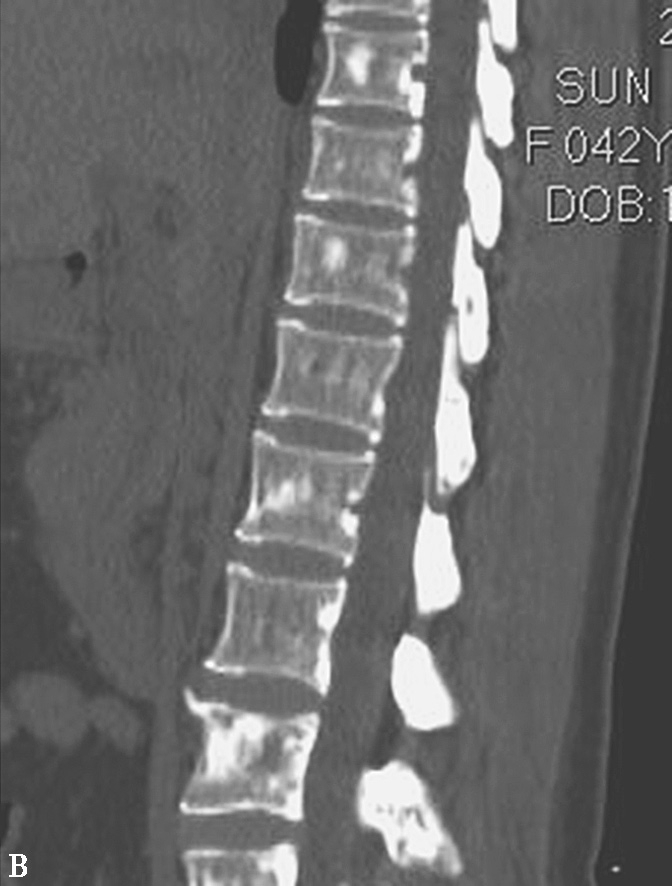

图1-7 结节性硬化

A.CT平扫;B.腰椎矢状位重组,示双侧侧脑室室管膜下、右额叶及右枕叶多发大小不一钙化结节,下胸椎及腰椎椎体内可见类似结节灶